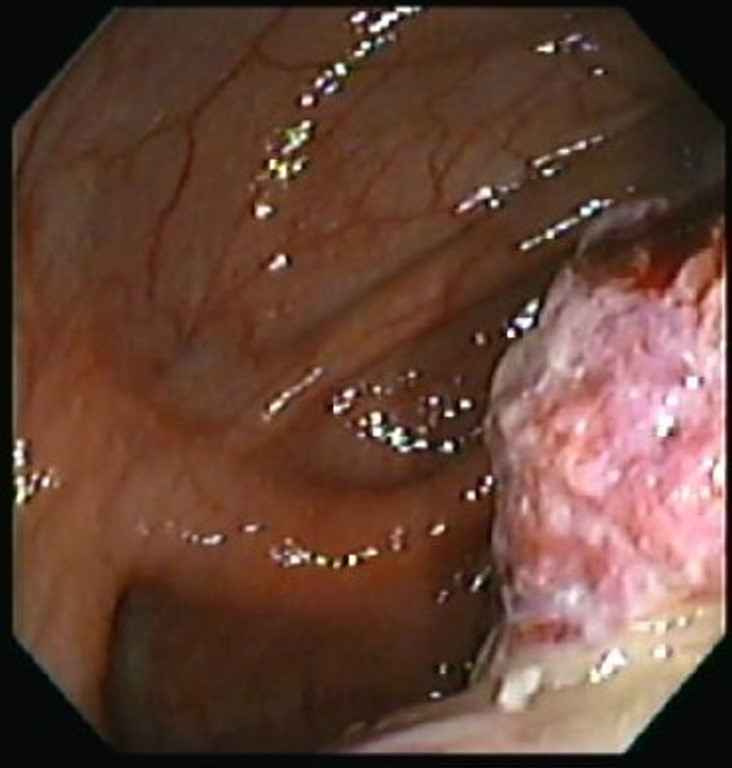

Cáncer de Colon

Envíado por Dr. Carlos Ernesto Arévalo